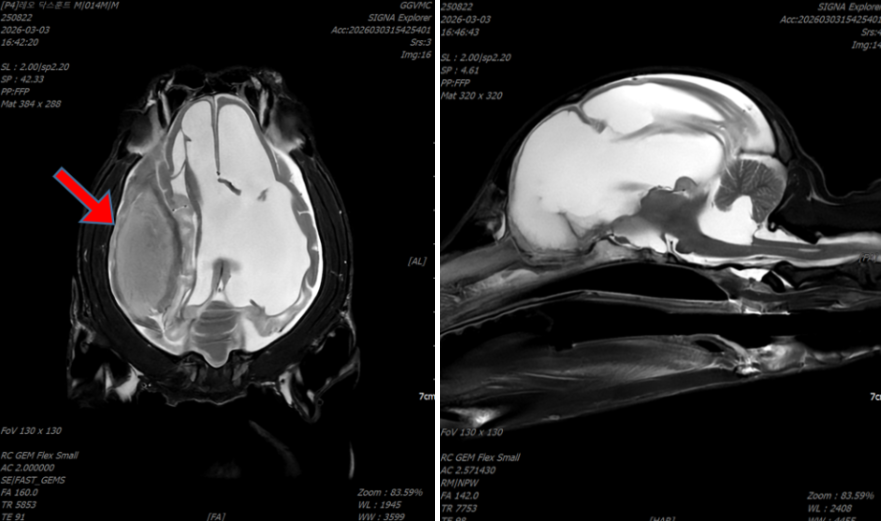

- CT 검사에서는 두개골 골절선이 확인되었으며,

- MRI 검사에서는 두개강 내 혈종과 함께 뇌실 확장이 확인되었습니다.

1. 외상 이후 발생한 강아지 뇌출혈이 장기간 지속되면서 혈종이 형성되고,

2. 이 혈종이 뇌를 압박하면서 뇌압 상승과 발작을 유발한 경우였습니다.

3. 또한 혈종이 뇌척수액의 흐름을 방해하면서 뇌실이 확장되는 이차성 뇌수두증으로 진행된 것으로 판단되었습니다.

<좌: 수술 전, 우: 수술 후>